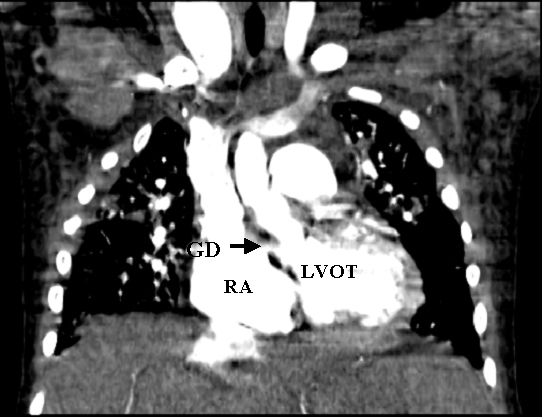

A seven-year-old girl presented to the emergency room (ER) with a six-day history of nausea, vomiting, and fevers. She has a history of aortic coarctation repair at 6 months of age. Symptomatically, she did well after that surgery, but had been followed for a residual coarctation. She presented to the ER hypotensive and was given three boluses of fluid and subsequently started on dopamine and transferred to the Pediatric Intensive Care Unit. Her C-reactive protein (CRP) and erythrocyte sedimentation rate (ESR) were elevated. Her physical exam revealed a V/VI holosystolic ejection murmur heard over the entire sternal border and diffuse crackles. An electrocardiogram revealed sinus tachycardia without heart block. Her blood culture on admission grew methacillin sensitive Staphylococcus aureus. She was started on Vancomycin and Cefotaxime. Cardiology was consulted secondary to her history of congenital heart disease and the possibility of endocarditis. An echocardiogram revealed a large mass in the RA located superior to the tricuspid valve septal leaflet and moderate to severe tricuspid valve regurgitation (TR). There was question of a left to right shunt from either the LV or aorta to the RA. A computed tomographic (CT) angiogram of the chest demonstrated there was a connection between the LV and RA, minimal residual coarctation, and an embolus occluding the left pulmonary artery (PA) (Figures 1, 2a, and 2b). She had persistent bacteremia and septicemia despite antibiotics, with progressive pulmonary edema. Less than 24 hours after cardiology was consulted, the patient was emergently taken to the operating room with the diagnosis of an acquired Gerbode defect and pulmonary embolism.

Figure 1. Computed tomographic scan showing left ventricle to right atrial shunt (arrow)

RA= right atrium; LVOT= left ventricular outflow tract; GD = Gerbode Defect

Preoperative diagnosis of an LV-RA communication is often very difficult. TEE has been demonstrated to be superior to trans-thoracic echocardiography (TTE) in identifying not only vegetations and valvar pathology, but also associated complications of endocarditis such as abscess and fistula formation [5]. In our patient, the preoperative diagnosis of a vegetation and an LV-to-RA communication was suspected by TTE, however the vegetation in the right atrium was not the typical oscillating type but rather a fixed mass just above the TV. This appearance can be typical for an aortic or ventricular to atrial shunt as echogenic debris builds up in this area of turbulent flow creating a windsock, as seen here (Figure 4a). Since the diagnosis remained unclear, a CT was performed primarily to assess the prior coarctation repair, but also we hoped it would better define the possible intracardiac shunt. The CT clearly identified the LV-to-RA shunt but also revealed a large pulmonary artery embolus (Figures 1-2). CT scan and MRI are diagnostic options in addition to echocardiogram in this disease process, especially as the speed at which one can obtain and perform a cardiac MRI continues to improve.